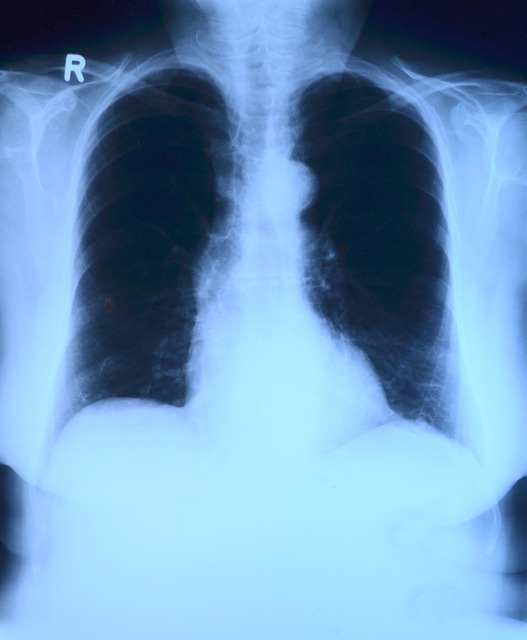

- 흉부 X-ray 검사

기본적인 폐 검사로 이상이 있을 경우 추가 검사가 필요하며, 조기 폐암은 발견이 어려울 수 있습니다. - 저선량 CT 검사